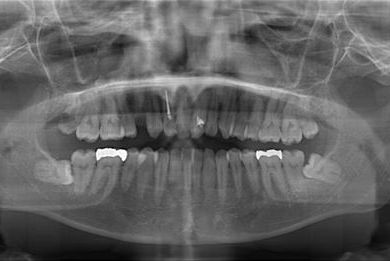

インプラント治療+セラミック治療

| カテゴリー | 【インプラント治療】【セラミック治療】 | ||||||||||||||||||||||||||||||||

| 性別/年齢 | 女性 / 30歳 | ||||||||||||||||||||||||||||||||

| 主訴 | 虫歯を治して欲しい。 | ||||||||||||||||||||||||||||||||

| 治療内容 | インプラント1本、メタルボンドセラミッククラウン1本、オールセラミッククラウン2本(オールセラミック用土台2本) | ||||||||||||||||||||||||||||||||

| 総治療費 | 703,238円 | ||||||||||||||||||||||||||||||||

| 治療期間 | 1年6ヶ月 |